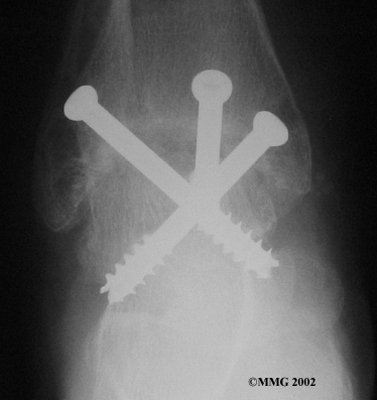

It is important when the surfaces are removed that the angles of the cut surfaces are correct. When the tibia is brought against the talus, the foot should be at a right angle to the lower leg. Once the cuts are made the bones must be held in place while they fuse. This can be done using large metal screws and metal plates if necessary. The screws are usually under the skin and are not removed unless they begin to rub and cause pain.

Inserting the screws

After ankle fusion, the physical therapists at FYZICAL Therapy & Balance Centers-East Flint can help you learn to walk smoothly and without a limp. Although time needed for recovery varies among patients, an ankle brace will typically replace your cast after eight to 12 weeks. Your surgeon will take X-rays frequently to see if the bones are fusing together. You will probably need to use crutches during the time you wear the cast. As the fusion grows stronger, you will begin to put more weight on your foot when walking.